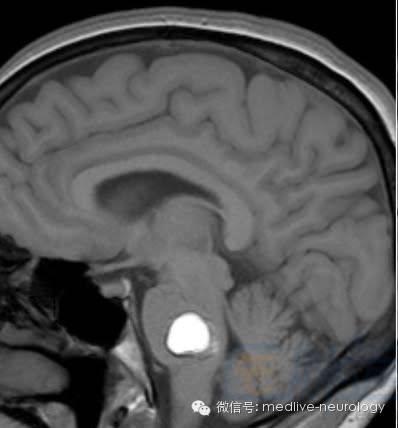

然后解决第三个问题,轻松一下,图来啦,让我们巩固一下今天学习的成果,均为先T1,后T2。

亚急性晚期(7-14d): 左硬膜下

慢性期(>14d):箭头